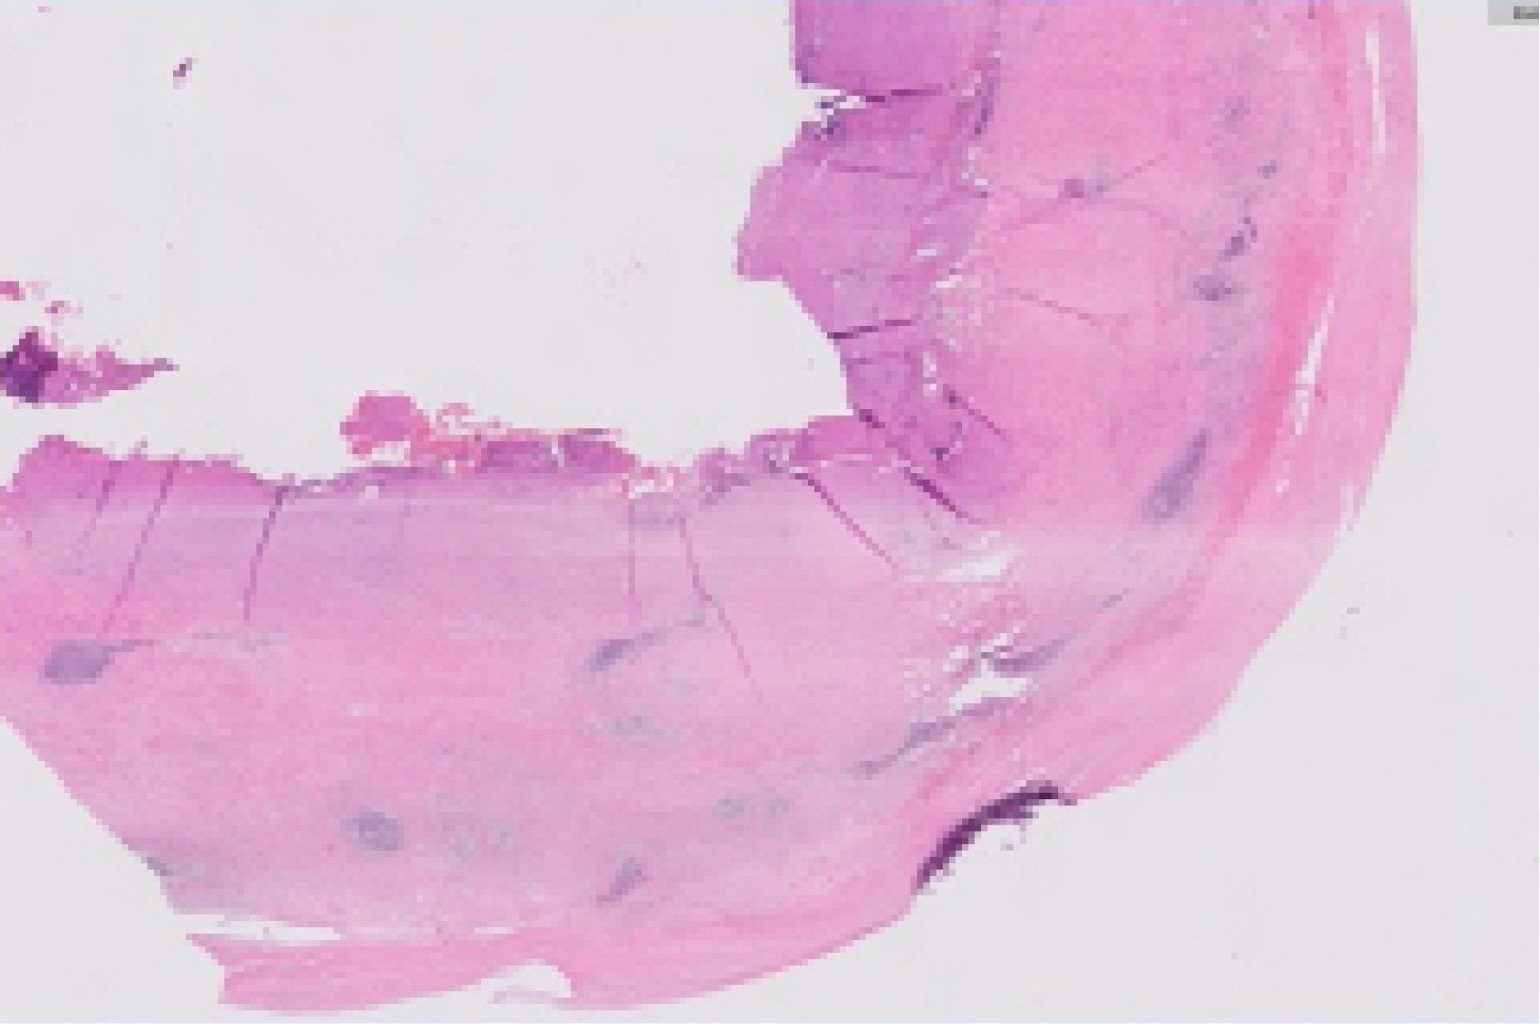

Introduction: the porcelain gallbladder represents a rare entity and it's associated with risk of malignancy. The treatment of choice is cholecystectomy, representing a surgical challenge given the degree of inflammation and fibrosis that this entity entails. Clinical case: we present a 56-year-old female with a history of recurrent episodes of biliary colic. She presents abdominal pain in the right hypochondrium of 7 hours of evolution, VNS (verbal numeric scale) 7/10 and nausea. Surgical treatment with laparoscopic cholecystectomy was decided. A gallbladder with a high degree of fibrosis, pearly color and adhesions to the omentum was found, a subtotal cholecystectomy was decided. Intraoperative retrograde cholangiography shows bile leakage from cystic duct and stent placement is performed. Conclusion: porcelain gallbladder is a histopathological condition in which there is calcification that infiltrates the gallbladder tissue. Found in 95% of cases of gallbladder lithiasis and represents special difficulty by limiting the field of vision due to its high degree of fibrosis. The prognosis depends on the degree of inflammation and the presence of malignancy. This entity entails a diagnostic and surgical challenge where the use of safe surgical alternatives for the patient becomes primordial, the technical knowledge and use of subtotal cholecystectomy is necessary for every surgeon who plans to perform laparoscopic cholecystectomy.

Figure 1